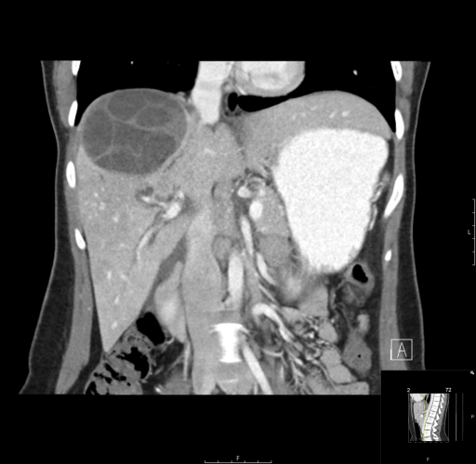

CASE 3 – A 23-year-old woman presents with 3 weeks of right upper quadrant (RUQ) pain associated with early satiety. The patient has no significant past medical history. She was born in Iraq and migrated to Australia from Syria 2 years prior to presentation. Preliminary blood results demonstrate moderate liver function test (LFT) derangement.

EXPLANATION -The case demonstrates classical appearance of a hepatic hydatid cyst. There is a well-defined rounded lesion in right lobe of liver with multiple small daughter cysts within. The fluid in the cysts can be of variable density depending on the proteinaceous contents (more protein = more dense). The thick internal septae can give a “spoke wheel” appearance as in this case. Curvilinear calcifications represents the inactive stage of the disease.

Hydatid diseases a parasitic zoonosis, caused by the larval stages of the Echinococcus granulosus .

- E. granulosusis found worldwide, however the highest rates of infection are seen in the Mediterranean and Middle Eastern regions, North Africa and South America.

- Hydatid cyst can occur anywhere in the body, the most commonly affected organ is the liver (76% of cases), followed by lung (15%) and spleen (5%).

- Classically there is a large ‘parent cyst’ which contains numerus peripheral ‘daughter cysts’.

- Humans are infected by eating the eggs of the tapeworm E. granulosus, by either eating contaminated food or through contact with dogs.

- The ingested embryos invade the intestinal mucosal wall, enter the portal circulation and develop cysts in the liver.

- Treatment options ; Surgical excision, PAIR (Puncture, Aspiration, Injection of protoscolicidal agent and Re-aspiration), Anti-helminthic agent (e.g. albendazole, mebendazole), Observation only – for inactive and silent cysts